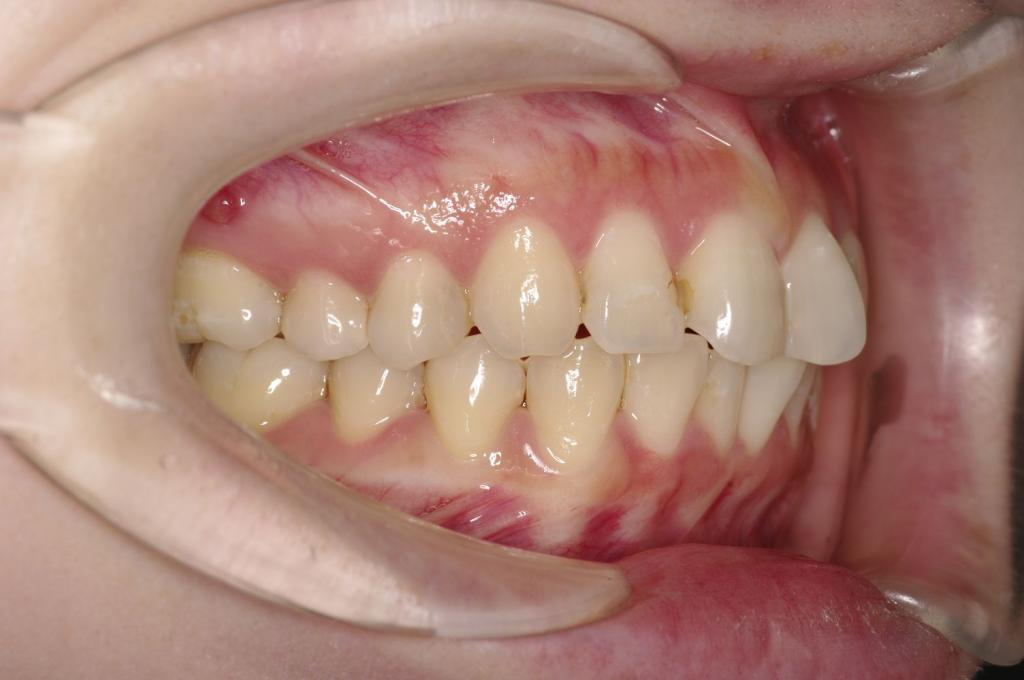

前歯、出っ歯・開咬の矯正治療

(治療期間、治療前後写真、治療方法、費用)WORKS